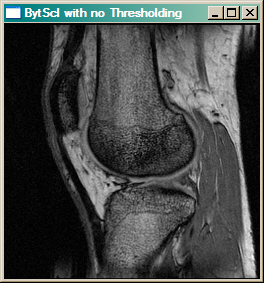

For example, the image below on the left is displayed with just the BytScl command, like this.

IDL> cgImage, BytScl(knee)

Whereas the image on the right uses a minimum threshold value of 1080 and a maximum threshold value of 1200.

IDL> cgImage, BytScl(knee, MIN=1080, MAX=1200)

When thresholding, all values in the image below the minimum threshold value are set to the threshold value before linear scaling occurs. Similarly, all values in the image greater than the maximum threshold value are set to the maximum threshold value before scaling. Notice the difference in contrast in the resulting image.